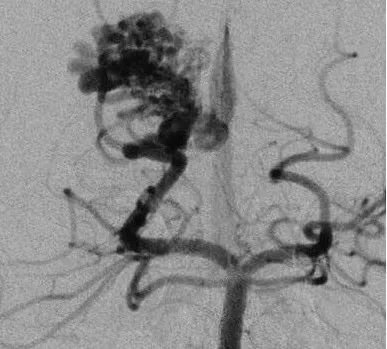

患者案例2:17岁男孩,表现为来自于右侧胼胝体压部AVM的脑室内出血(补充Spetzler-Martin分级4级:S1V1E1/A1B0C0),SplenA供血,SplenV和内侧AtrV引流右椎动脉造影。

(a)侧位(b)前后位].(c)他取侧卧位,右侧朝下,鼻朝下,中线取水平位以便靠重力牵拉右侧枕叶。窦汇开颅,显露SSS、TrvS、枕较、后纵裂和镰幕交界处。SplenA沿胼胝体压部上升,顺着它可达AVM(续)。